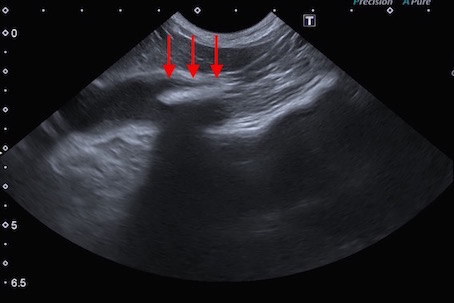

超音波検査所見です。

胃から出たすぐの十二指腸に怪しい影(赤矢印)が確認されました。また、胃および十二指腸に液体貯留所見(消化管の流れが悪いこと)も認められました。